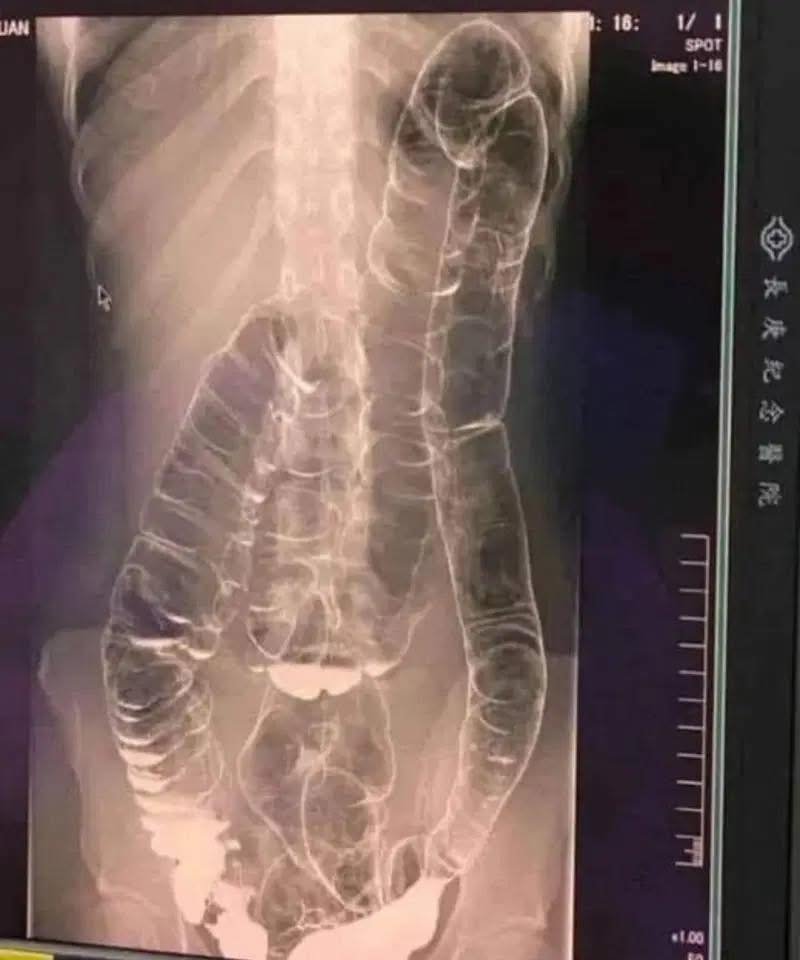

This is an X-ray of a young woman suffering from chronic constipation. After experiencing persistent symptoms for more than two weeks, she consulted a doctor and received the results of the X-rays below…

Who hasn’t encountered constipation? This problem, often perceived as trivial, can transform into a real nightmare if it becomes constant. This is exactly what occured to a young woman whose overloaded colon ended up dangerously dilating. So, how can we prevent this digestive disorder from taking a noticeble turn?

When you don’t have regular bowel movements, waste builds up in the colon. The result: extra pressure that can cause pain, bloating , and, in severe cases, terrible complications.

Colon distension: Over time, the colon weakens its elasticity and becomes increasingly difficult to remove stools.

Bowel obstruction: In extreme cases, fecal matter can completely block the intestine, demanding emergency surgery .